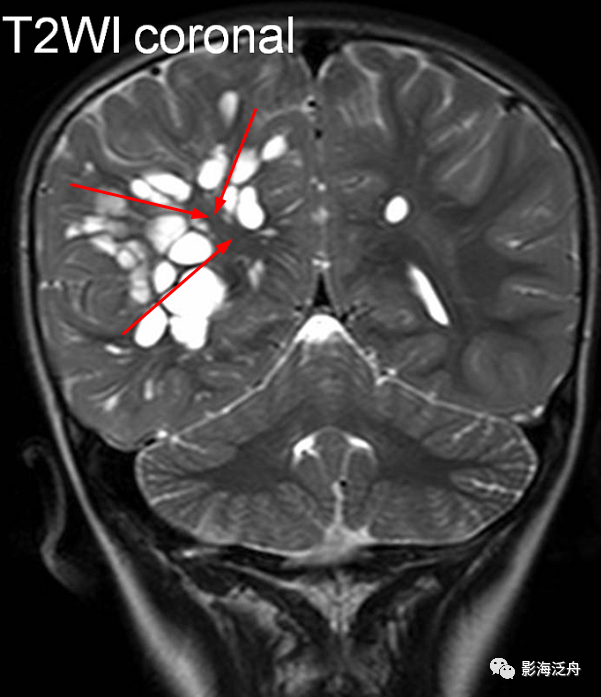

图片

当脱髓鞘改变呈片状且沿着侧脑室周围对称性分布时,大家往往一眼就能识别出来,像上图这种双侧半卵圆中心多发非特异性脱髓鞘病灶,大家可能就有点心虚了。注意最大的一个病灶(黄箭)长轴平行于侧脑室(红线),所以只是普通的退变,而不是不是MS。

当这种非特异性脱髓鞘病灶比较局限、散发的时候,如何与VR腔隙及腔梗灶区分呢?一般来说,前者显示比后两者更加浅淡和模糊,在T1WI序列尤为明显。